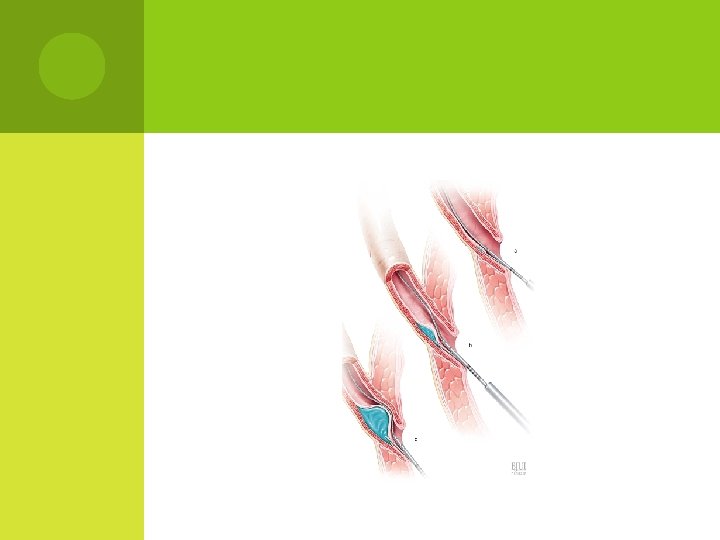

I NTERVENTIONALTREATMENT endoscopic injection of bulking agents

ENDOSCOPICINJECTIONOF BULKING AGENTS With the availability of biodegradable substances, endoscopic subureteric injection of bulking agents has become an alternative to long -term antibiotic prophylaxis and surgical intervention in the treatment of VUR in children.

BULKING AGENTS : polytetrafluoroethylene (PTFE or Teflon), collagen, autologous fat, polydimethylsiloxane, silicone, chondrocytes and, more recently, a solution of dextranomer/hyaluronic acid (Deflux).

BULKING AGENTS : bulking agents dextranomer/hyaluronic acid (Deflux) was FDAapproved for the treatment of VUR in children.

Endoscopic injection for vesicoureteral reflux. reproduced from Deflux® patient education brochure (Q‑Med, Uppsala, Sweden) Cooper, C. S. (2009) Diagnosis and management of vesicoureteral reflux in children Nat. Rev. Urol. doi: 10. 1038/nrurol. 2009. 150